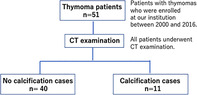

FIGURE 1.

Patients with thymomas (n = 51) who were enrolled at our institution between 2000 and 2016. All patients underwent CT examination. No calcification cases were 40 patients and calcification cases were 11 patients